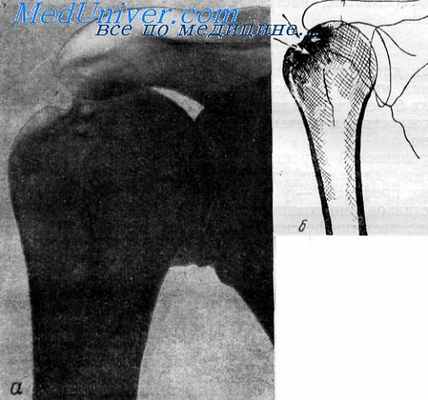

Обызвествление слизистой сумки на типичном месте с начальным краевым склерозом головки правого плеча у 49-летней машинистки с 25-летним стажем.

Рентгенограмма (а) и схематический рисунок (б) правого плечевого сустава. Краевая резорбция и склероз в области бугорков плечевой кости 59-летнего рабочего тяжелого физического труда.